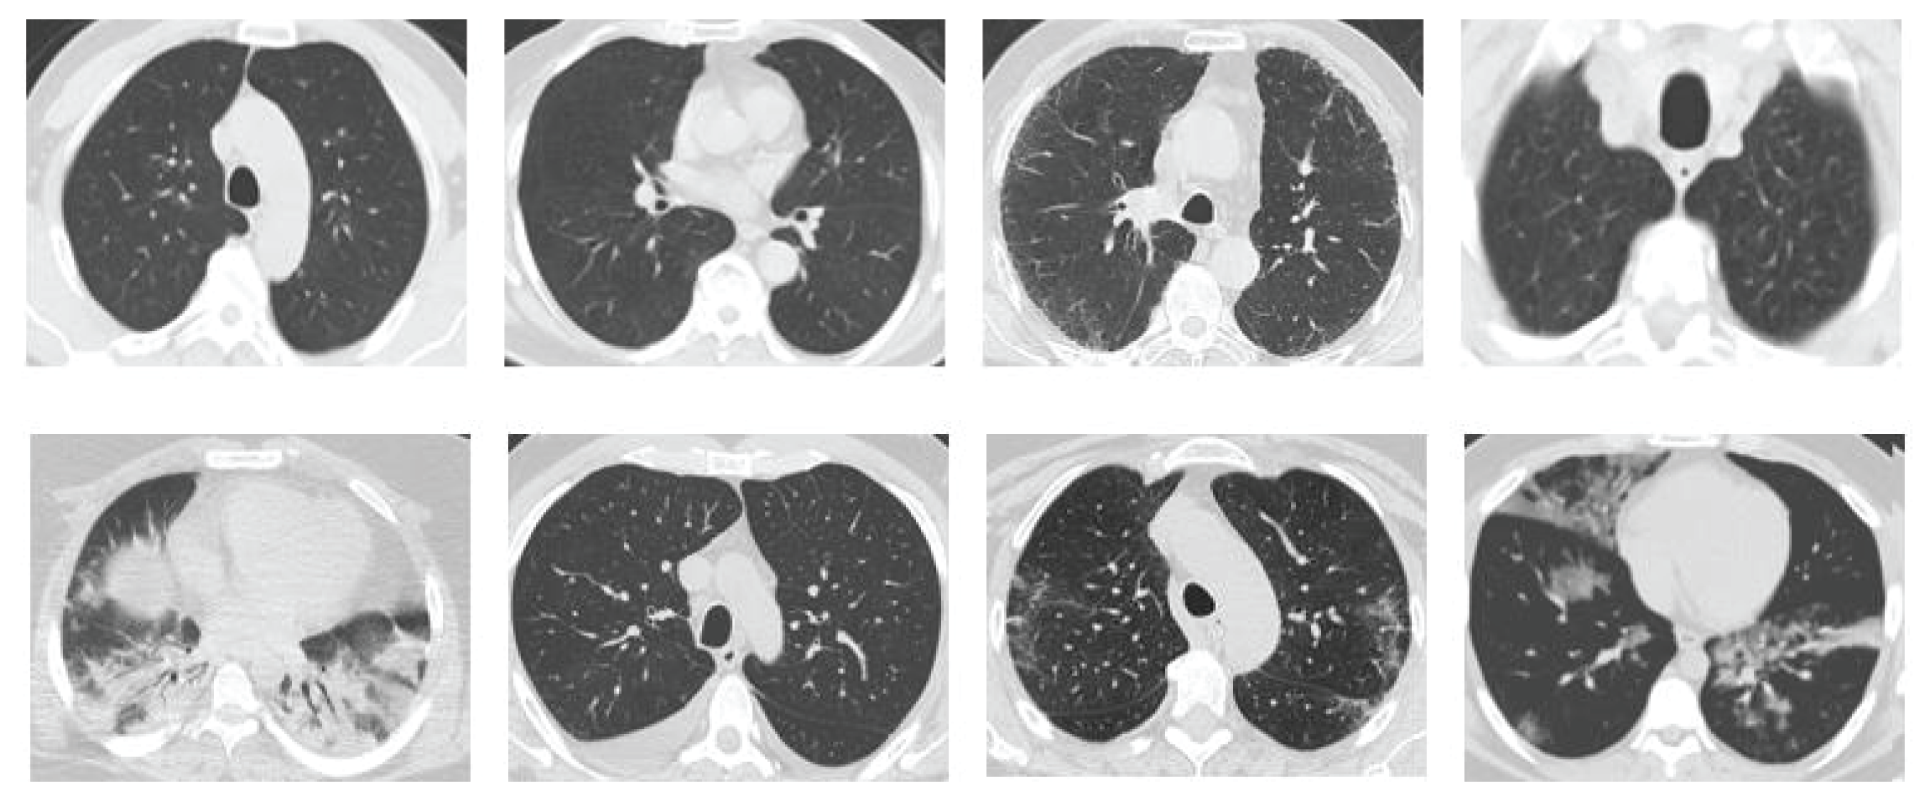

Due to the rapid spread of COVID-19 and the need for a rapid response to this disease, several CT datasets were utilized by deep learning-based applications to analyze and detect COVID-19. However, there is scarcity of publicly available datasets, such as the SARS-CoV-2 CT scan dataset proposed by Soares et al. [19], which is used in this study to evaluate the proposed model. SARS-CoV-2 CT scan dataset is one of the widely publicly available datasets. This was obtained from the hospitals in Sao Paulo, Brazil [19]. Moreover, this dataset is composed of 2482 CT scan images (1252 CT scan images of 60 COVID-19 patients and 1230 CT scan images of 60 non-COVID-19 patients). The detailed characteristic of each patient has been omitted by the hospitals due to ethical concerns. Fig. 6 presents some examples of the CT scan images of COVID-19 and non-COVID-19 patients, which compose the dataset.

Figure 6: Sample images from the CT dataset. The images in the first row are those of non-COVID-19 patients, whereas the images in the second row are those of COVID-19 patients